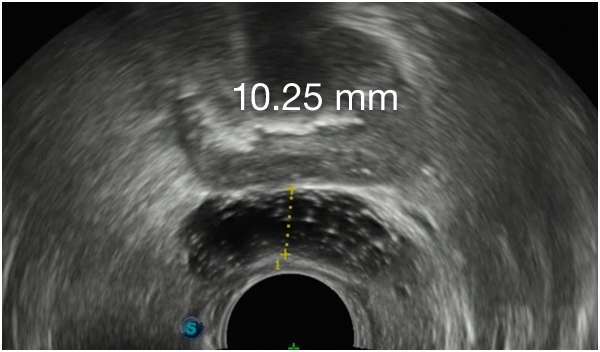

ACHIEVE CONSISTENT RESULTS

WITH BARRIGEL SPACER3,8,9

ACHIEVE CONSISTENT RESULTSWITH BARRIGEL

SPACER3,8,9

First Barrigel Spacer Cases - Consecutive Patients (Same Day)

TRUS images courtesy of Daniel R. Welchons, MD

Urologist; New York, United States

Results may vary.

DR. WELCHONS’ INJECTION TECHNIQUE